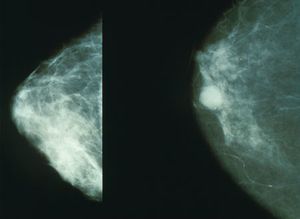

الغرسات ومسح الثدي